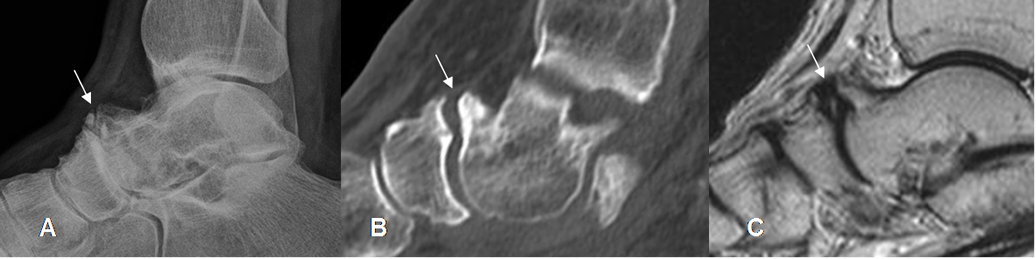

Fig 130 A. Artropatía degenerativa.

A: Rx lateral, B: TAC reconstrucción sagital y C: RM sagital en T2. Presencia de cambios degenerativos, con formación de osteofitos en la articulación taloescafoidea.